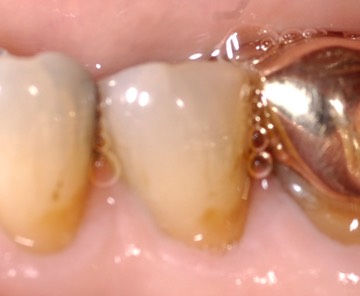

Photos of Clinical Operations

_DSC4989_1